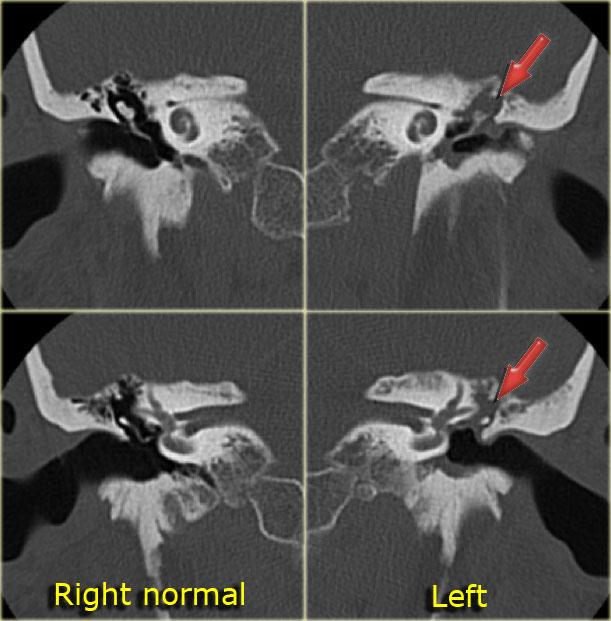

Hình ảnh bên trái của một nam bệnh nhân bị chấn thương đầu hai tháng trước.

Bệnh nhân than phiền về ù tai từng cơn.

Có đường gãy dọc (mũi tên vàng) đi qua xương chũm về phía vùng hạch gối.

Có trật xương đe với trật khớp búa-đe và khớp đe-bàn đạp (mũi tên xanh).

Không có tổn thương tai trong.

Tai trái để so sánh.